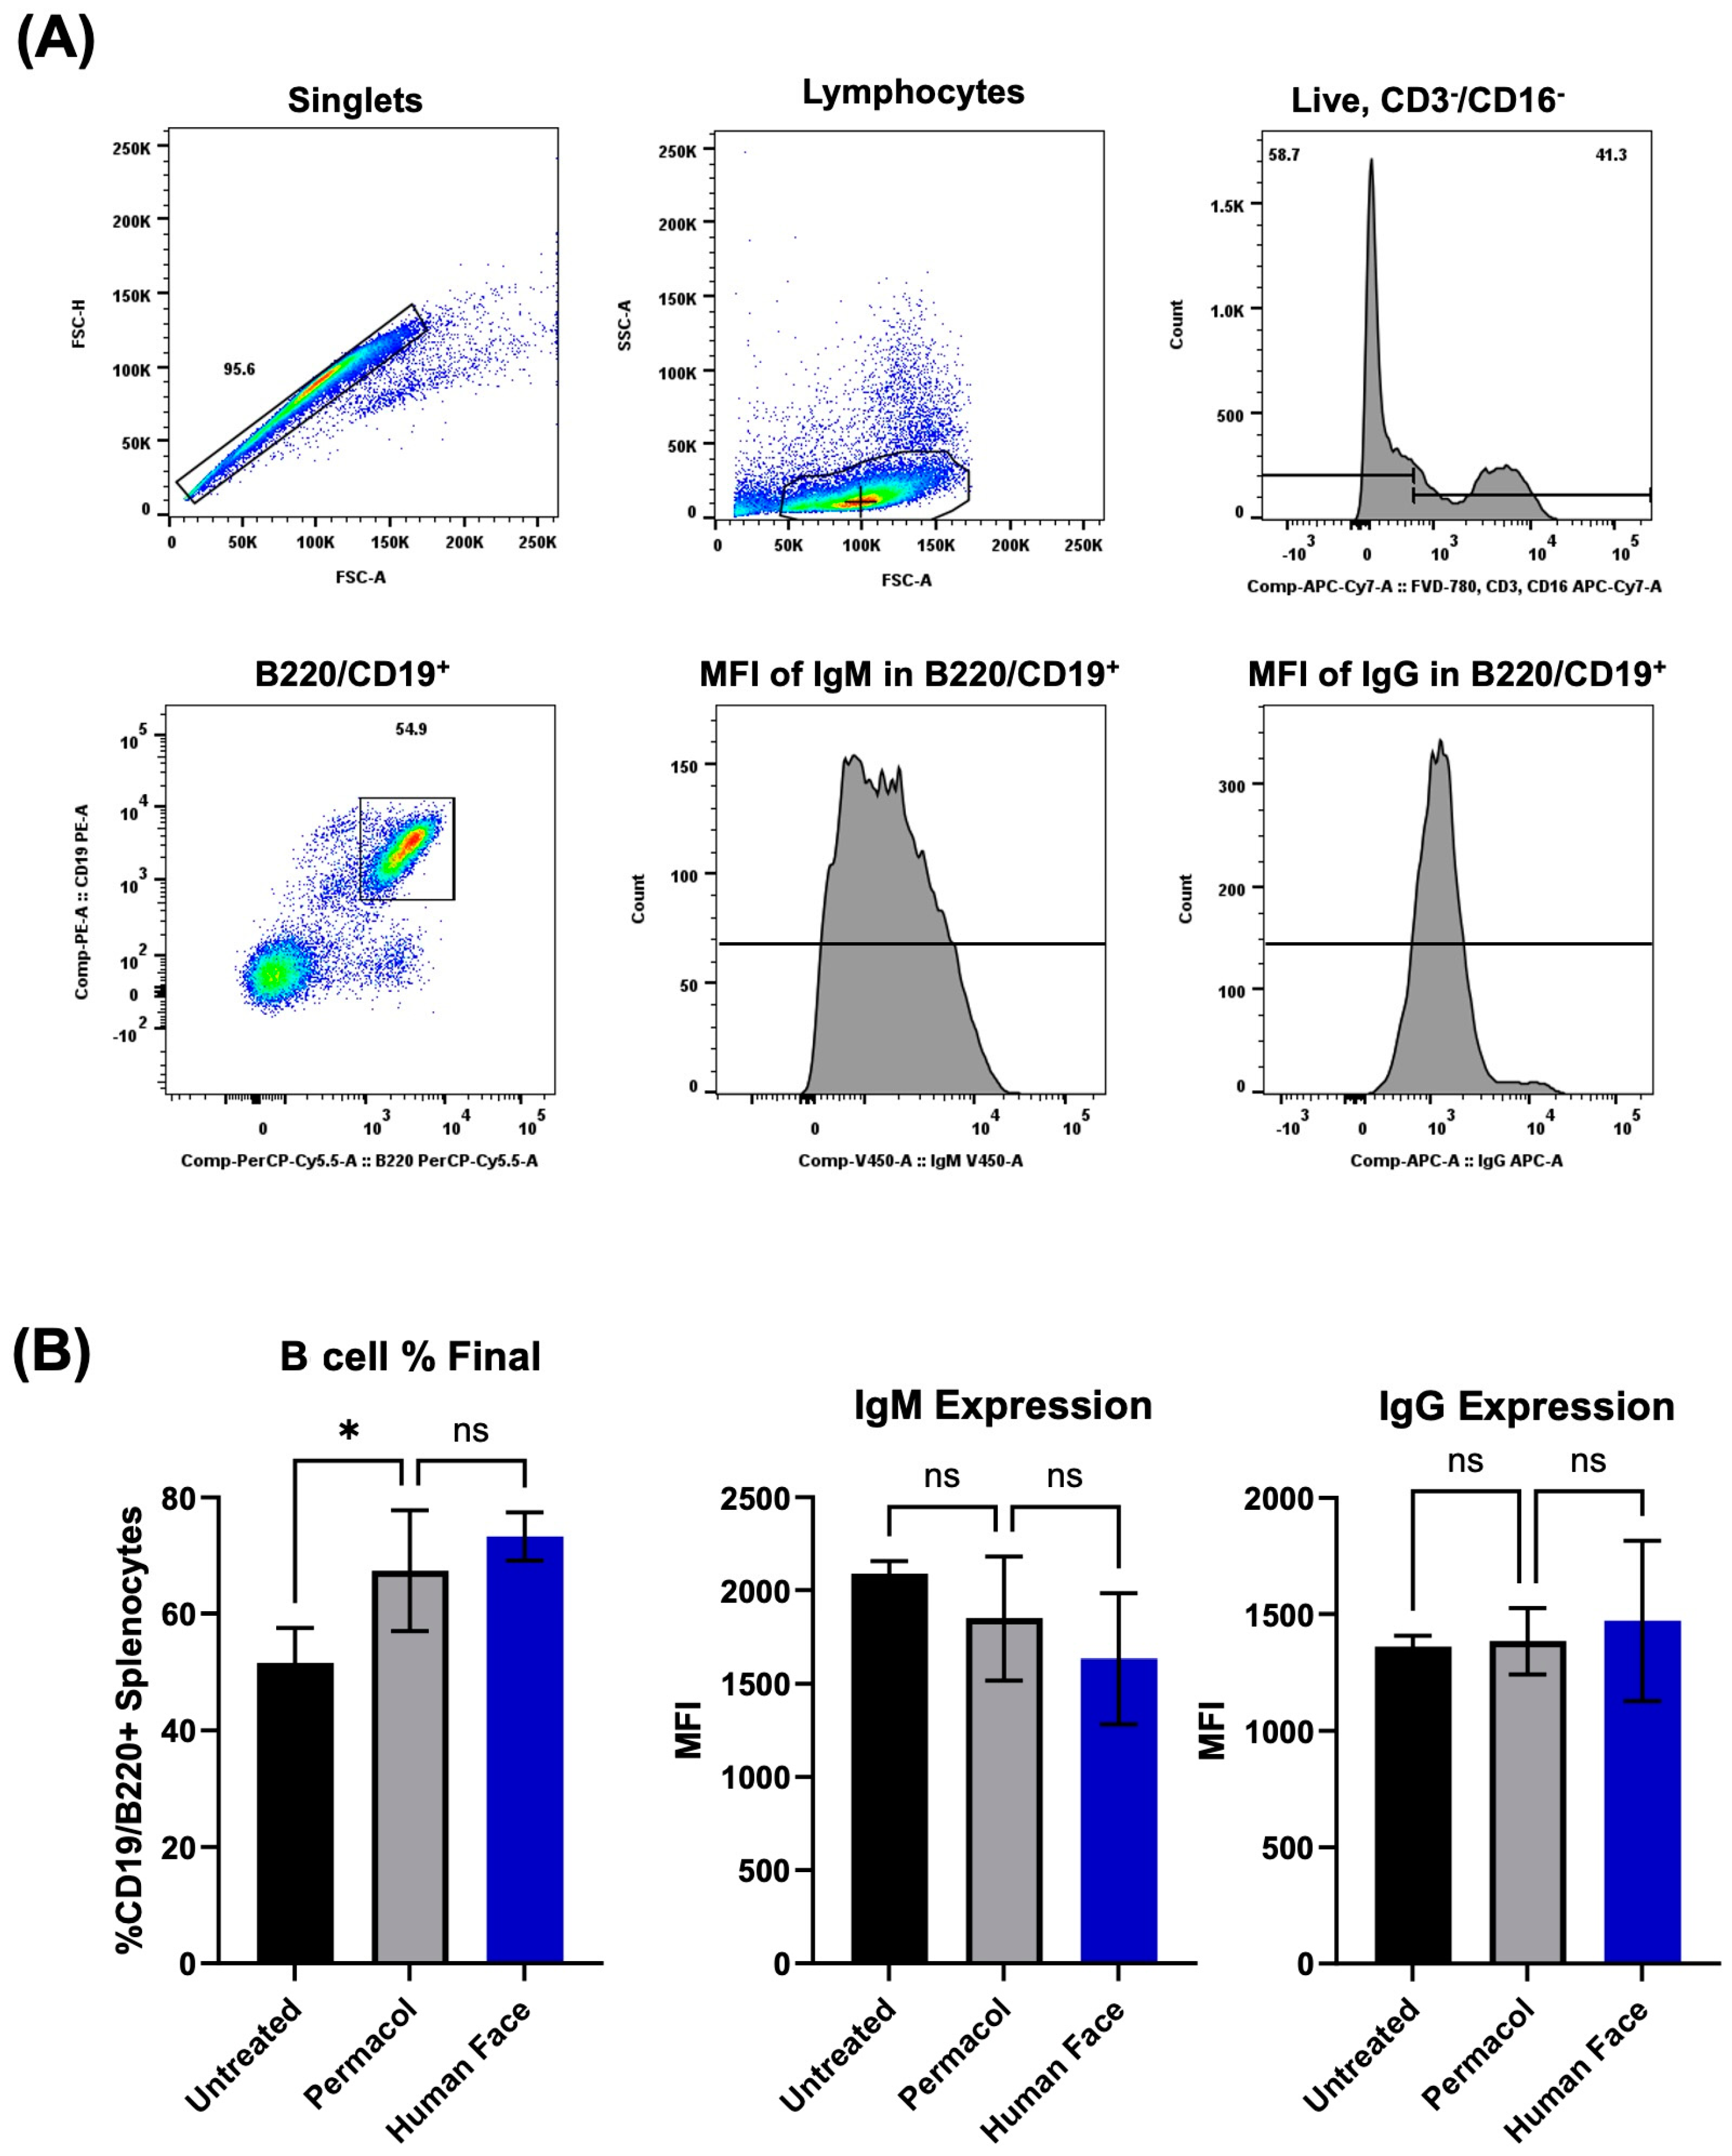

3.4. In Vitro and In Vivo Biocompatibility of Decellularized Facial Grafts